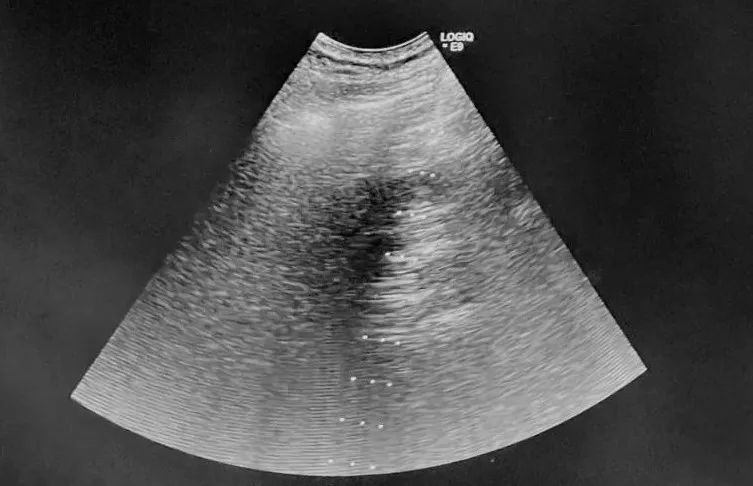

各相关科室专家经过MDT小组讨论,为这例肝癌患者制定了个体化方案。先局麻下超声引导经皮肝脏肿瘤射频消融治疗控制肿瘤进展,再适时行冠脉支架治疗,冠心病改善后再择期行腹腔镜胆囊切除术。肝癌射频消融治疗于局麻下实施,将心血管风险降至最低,又能很好的控制肿瘤,对于3cm大小肝癌甚至达到手术切除效果。患者及家属心情非常激动,消除了顾虑,安心等待治疗。患者因高龄,术前评估的项目较多,住院等待时间延长,又临近春节,心理变得急躁,担心术后恢复还需要时间,不能回家过年了。普外科毕敬涛副主任对患者心情感同身受,一边安抚患者情绪,一边联系超声科陈涛主任,协调手术时间。超声科三院区日常诊疗工作已经超负荷运转,工作时间内诊室全部占用,不好协调时间,射频治疗还需要等待。当超声科陈涛主任得知患者及家属的实际需求和迫切心情,和普外科毕敬涛主任协商后,毅然决定加班为患者安排治疗。

1月17日,陈涛主任下班后,时间已经很晚了,本想跟患者及家属协商更改手术时间,但为了患者安危,为了家属安心,陈主任毅然从新街口院区赶往回龙观院区。经过充分准备,晚7点多手术开始。超声科陈涛主任熟练地操控超声探头进行引导,由普外科毕敬涛主任负责穿刺,普外科孔娜主治医师和荀晓冬住院医师配合,最终顺利完成经皮肝肿瘤射频消融术。患者痛苦很小,操作过程顺利,患者及家属万分感激。